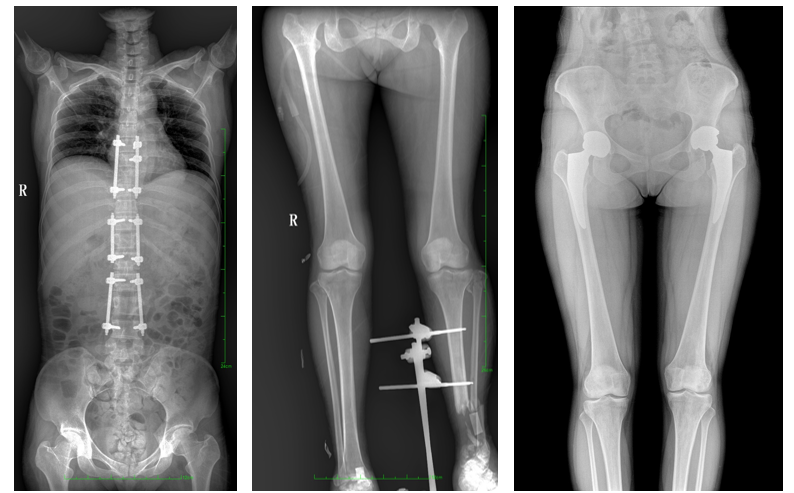

一、成像面積大。17"*34"有效視野,一次成像不拼接。相較于多張攝影再軟件拼接的DR設備,PLX8600解決了拼接圖像存在密度不均勻,拼接處圖像配準和放大效應等問題,給臨床帶來了大視野影像解決方案,可一次性覆蓋全脊柱或雙下肢影像。

PLX8600大視野平板動態DR攝影速度快,患者可以更快地完成檢查,且單次攝影輻射劑量是常規多張攝影再軟件拼接DR的1/2或1/3,低劑量給患者更多關愛。